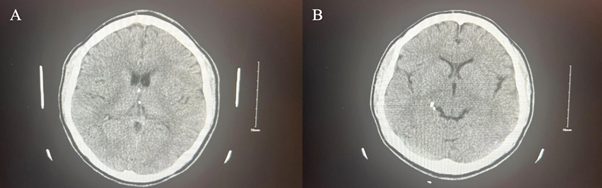

A 25-year-old male immigrating from Ecuador was brought into the emergency department by EMS activated by his father for aggression at home and changes in his behavior. The patient had arrived from Ecuador in January 2023 and the family stated that since then he had stopped showering, stopped eating regular meals, and has lost about 30 pounds. The patient had no known past medical history, no known past psychiatric history, or inpatient psychiatric admissions. However, he did have a history of mandibular fracture repair in 2022 after suffering a TBI during an assault in Ecuador. During his hospitalization, the patient was noted to have marked tangentiality in his speech and was evasive to interview questions, often providing vague answers. It was noted that the patient was disheveled, had poor hygiene, and refused to shower. At the time it was seen that he was inappropriately laughing and smiling. Later, during his stay in the inpatient facility, he endorsed that he had been planning to move back to Ecuador. However, on the day of admission, he saw multiple black cars outside of his home and felt that people were waiting for him to come out. During his stay in the inpatient unit, it was observed that he was guarded and suspicious, often facing the window during mealtime, not engaging with peers, and continued to exhibit poor hygiene. He denied any active mood symptoms concerning depression or mania. Throughout his stay, he appeared to be internally preoccupied. As stated previously his past medical and psychiatric history were negligible, but he did have a history of using cannabis. Overall, throughout the patient's 30-day stay in inpatient, his vitals were stable. The patient's psychosis was treated with risperidone, and towards his discharge he was switched to the long-acting injectable antipsychotic, paliperidone. As his stay in the hospital progressed, the patient's psychotic symptoms, such as paranoia and delusions, mildly improved, but his baseline continued to be guarded and avoidant of other patients until his discharge day. Lab workup included CBC, CMP, and toxicology screen. CBC showed a slightly low range but insignificant values of hemoglobin, hematocrit, and white blood cell count. The CMP showed no electrolyte abnormalities, revealing an elevated ALT, AST, and ALP. The urine toxicology screening revealed he was negative for opioids, cocaine, amphetamines, PCP, THC, barbiturates, and benzodiazepines. Non-contrast head CT imaging was obtained, and this demonstrated punctate dystrophic calcifications in the right ambient cistern and the third ventricle (See Figure 2 and Figure 3). These lesions as shown in Figures 2 and 3 were interpreted to be possibly caused by neurocysticercosis. Serology performed with an Enzyme-linked Immuno-Electro Transfer Blot (EITB) assay confirmed that the lesions are definitively caused by Taenia Solium. As a management plan, the antipsychotic treatment has been stopped, and antiparasitic albendazole has been considered in the treatment for active neurocysticercosis and its neuropsychiatric manifestations.

Figure 3 Non-contrast head CT Transverse view. Images (A) shows punctate dystrophic calcifications in the third ventricle. Image (B) demonstrates calcifications in the right ambient cistern.

As the first impression, the medical team in the emergency department leaned towards a psychiatric disorder as a first differential rather than an infectious disease. From the patient's history, we learn that the patient also had a TBI which brings up degenerative disease secondary to traumatic event as a secondary potential differential making the suspicion of neurocysticercosis as the top differential low. What makes neurocysticercosis diagnosis complicated in early investigation is the fact that it has an acute to chronic timeline where multiple events can happen in between the exposure to the pathogen until the onset of signs and symptoms are manifested. We consider that this is a flagrant example of a disease presentation where life events can remarkably affect the incidence of schizophrenia spectrum disorder secondary to neurocysticercosis. The diagnosis of neurocysticercosis can be tricky and challenging. The physicians in the emergency department should proceed with a holistic approach and start with a thorough history, considering a collateral history especially from the patient's family since the information given by the family in case of neuro-psychiatric disorders and emergencies can be extremely accurate and helpful. The investigation should also promptly focus on blood work and neuroimaging techniques, such as MRI or CT scans, essential to visualize the cysts in the brain or spinal cord. Ultimately antibody serology test for Taenia Solium should be performed as a diagnostic confirmatory testing. Considering the non-contrast head CT images (Figure 2 and Figure 3) in our case, it showed calcified lesions which have been shown to be a sign of chronic cerebral cysticercosis. However, these calcified lesions which are secondary to granulomatous reactions can be considered a nonspecific sign because they can be seen in other illnesses such as previous toxoplasmosis. Thus, we highly recommend the rigorous use of guidelines for the clinical management of patients with neurocysticercosis (NCC) developed by a panel of the Infectious Diseases Society of America (IDSA) and the American Society of Tropical Medicine and Hygiene (ASTMH).9 These guidelines can be very helpful in the diagnosis process intended for infectious disease specialists, psychiatrists, neurologists, neurological surgeons, internists, pediatricians, and family practitioners. The neurocysticercosis-induced psychotic disorder is considered a rare disease, but many experts consider this due to it going unrecognized and thus underreported.8-12 Therefore, these guidelines are indeed a supportive framework for neurocysticercosis diagnosis, which might be very supportive in the diagnosis of neurocysticercosis challenging clinical presentations, as in the case we have seen in this paper.  This framework has been developed to be followed in the diagnostic process in which clear and comprehensive standards are provided and demonstrated and which are founded on a multidisciplinary clinical approach. Using these guidelines can help not only the clinicians in the investigation but also prevent complications and progression of symptoms and, eventually, patient suffering.8-12